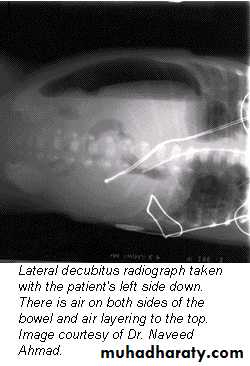

Positioning

• Lateral decubitus

The main purpose of horizontal beam films is to detect air-fluid levels and free intraperitoneal air